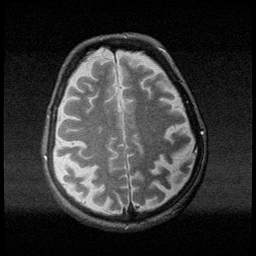

Huntington's Chorea, MR -- Slice #15

[Home][Help][Clinical] Slice 15